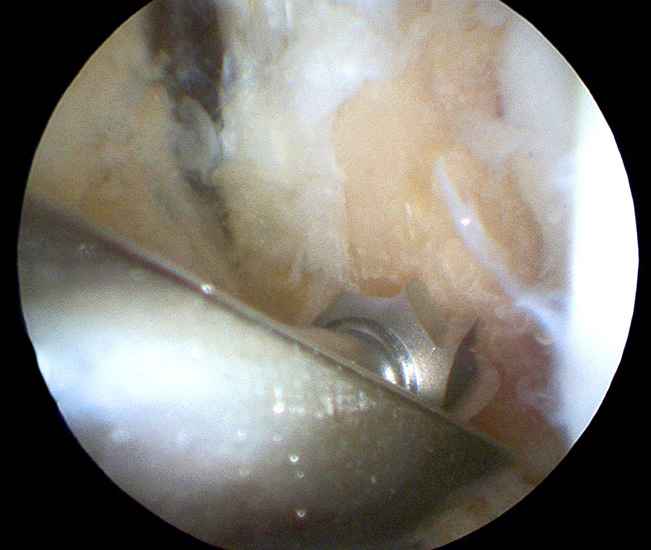

Nachfolgend wird die OP-Technik an einem rechten Sprunggelenk unter Verwendung von PEEK-Ankern veranschaulicht.

Intra- und extraartikuläre Darstellung des Operationsablaufs am linken Sprunggelenk mit selbstschneidenden Titanfadenankern.